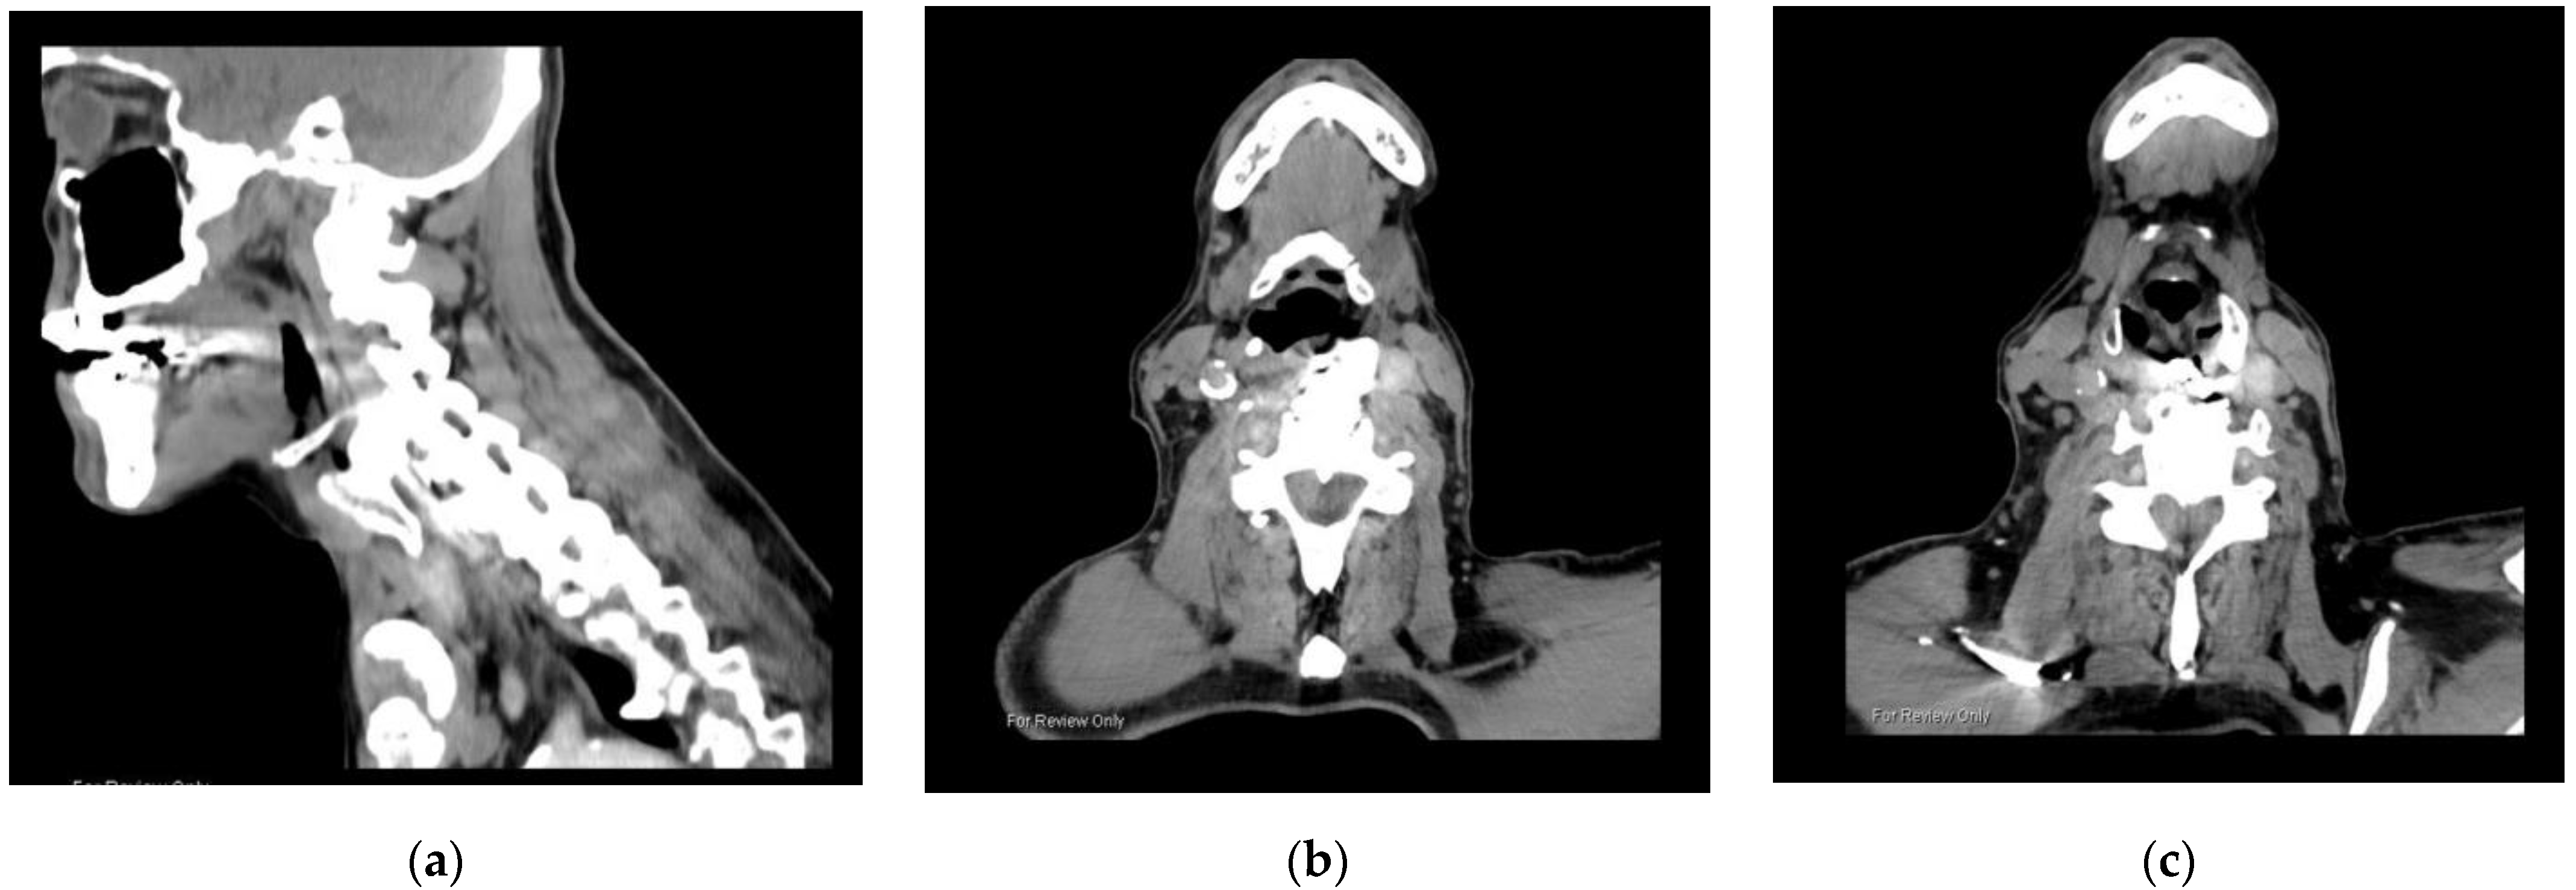

3.1.1. Case 1

3.1.2. Case 2